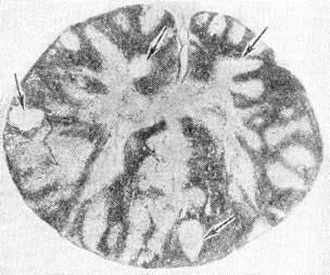

МиелополирадикулоневритМиелополирадикулоневрит (греческий myelos костный мозг+ poly [s] многочисленный + латынь radicula корешок + греческий neuron нерв + -itis) — распространённый воспалительный процесс, охватывающий спинной мозг, корешки и периферические нервы. Интенсивность процесса в указанных отделах различна. В ряде случаев сильнее поражается спинной мозг, в других — корешки и периферические нервы. Миелополирадикулоневрит не имеет нозологической самостоятельности, может возникать при инфекционных, аллергических заболеваниях нервной системы, а также при интоксикациях и энзимных дефектах. Миелополирадикулоневрит может также наблюдаться при вирусных заболеваниях нервной системы: остром рассеянном энцефаломиелите, опоясывающем лишае, полиомиелитоподобных заболеваниях, вызванных энтеровирусами (Коксаки, ECHO), клещевом энцефаломиелите, паралитических формах бешенства. Миелополирадикулоневрит иногда возникает при тяжёлом течении детских инфекций, например, при кори, ветряной оспе, эпидемическом паротите. Миелополирадикулоневрит инфекционно-аллергического генеза встречается после различных вакцинаций (антирабические, противооспенные прививки), после гриппа, при узелковом периартериите. Миелополирадикулоневрит могут быть проявлением бластоматозных процессов (например, миеломной болезни, лейкозов, лимфогранулематоза), глистных инвазий (шистосоматоза). Патологическая анатомия. В основе Миелополирадикулоневрит лежит своеобразный воспалительный процесс, охватывающий серое и белое вещество спинного мозга (смотри полный свод знаний), оболочки, паренхиму и строму спинномозговых корешков и периферических нервов (смотри полный свод знаний). Воспалительный процесс сочетается с очагами демиелинизации (рисунок 1) в различных отделах белого вещества спинного мозга, а также в корешках и периферических нервах. Демиелинизация происходит вокруг сосудов—так называемый перивенозная демиелинизация. Наблюдается лимфоидная инфильтрация стенок сосудов, происходит периваскулярный распад миелина, накопление жира в макрофагах. Помимо перивенозной демиелинизации, формируются очаги микронекрозов со слабо выраженной воспалительной реакцией. Основная масса нервных клеток спинного мозга сохраняется, они гибнут преимущественно в очагах демиелинизации (рисунок 2). Глиальная пролиферация отмечается в перивенозных очагах и сером веществе спинного мозга. Воспалительная реакция в оболочках выражена нерезко и носит вторичный характер. В корешках и периферических нервах наблюдается очаговая сегментарная демиелинизация и пролиферация леммоцитов (шванновской глии);вторичная дегенерация аксона (при гибели нервных клеток), в эндопериневрии инфильтрация стенок сосудов лимфоидными клетками и гистиоцитами. Постоянно отмечается отёк эпидурального пространства и эндо и периневрия корешков. Клиническая картина полиморфна. Основные признаки: болевой синдром, двигательные нарушения, расстройства чувствительности, нарушения функции тазовых органов, изменения цереброспинальной жидкости. Указанные явления возникают либо на фоне симптомов инфекционных заболевания (повышение температуры, головные боли, боли в пояснице, общее недомогание и другие), либо спустя 1—3 недель после перенесённой инфекции. Первые признаки Миелополирадикулоневрит — боли (спонтанные в конечностях), симптомы натяжения, парестезии, дизестезии (смотри полный свод знаний Чувствительность, расстройства). Одновременно или несколько позже возникают двигательные нарушения в виде парезов и параличей (смотри полный свод знаний Параличи, парезы), возможен паралич дыхательных мышц. На фоне общей мышечной гипотонии может отмечаться повышение тонуса отдельных групп мышц. В начальной фазе болезни может наблюдаться повышение сухожильных рефлексов (смотри полный свод знаний), позже возникает арефлексия (смотри полный свод знаний). Патологический рефлексы (смотри полный свод знаний Рефлексы патологические), клонусы (смотри полный свод знаний) отмечаются в начальной стадии болезни и в фазе восстановления двигательных функций. Расстройства чувствительности при Миелополирадикулоневрит постоянны и разнообразны: сегментарно-проводниковые грамм диссоциированные с преимущественным нарушением глубокой чувствительности. При исследовании цереброспинальной жидкости в остром периоде выявляется лимфоцитарный цитоз и умеренное повышение белка, в более поздних стадиях — белково-клеточная диссоциация. |